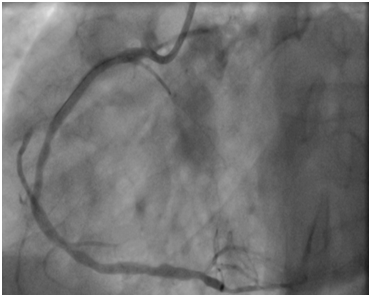

A 53year-old male without cardiovascular risk factor was admitted to our hospital in 2005 due to an inferior AMI. The culprit lesion was thrombotic occlusion of proximal right coronary artery (RCA). Primary percutaneous coronary intervention to RCA with a BMS (3.00x24mm; Liberté®; Boston scientific, Natick, Massachusetts) was done with an excellent result. No post-dilatation was needed. Dual antiplatet therapy was prescribed for one month (Clopidogrel 75mg once a day). Then; aspirin (ASA) was prescript alone for life. Eight years later, he suffered from a severe chest pain relevant to a recurrent inferior AMI. Hence, he was immediately referred for a primary angioplasty. In-stent huge thrombosis was located in the proximal edge of the stent of the RCA. IC stent® (Siemens Healthcare GmbHErlangen, Germany) had showed an underdeployment of the stent. Then, a predilatation with a non compliant Balloon had restored a TIMI III flow. He was discharged five days later with a daily 75mg of clopidogrel for 12months and 100mg of ASA associated daily for life (Figure 1-3).

Figure 3 Final result.